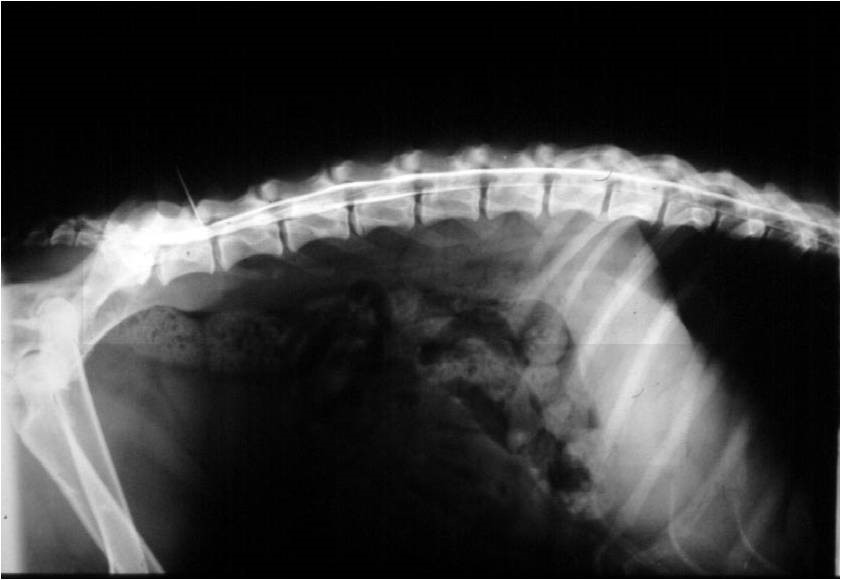

A nyak és a háti gerinc szakasz átmenete